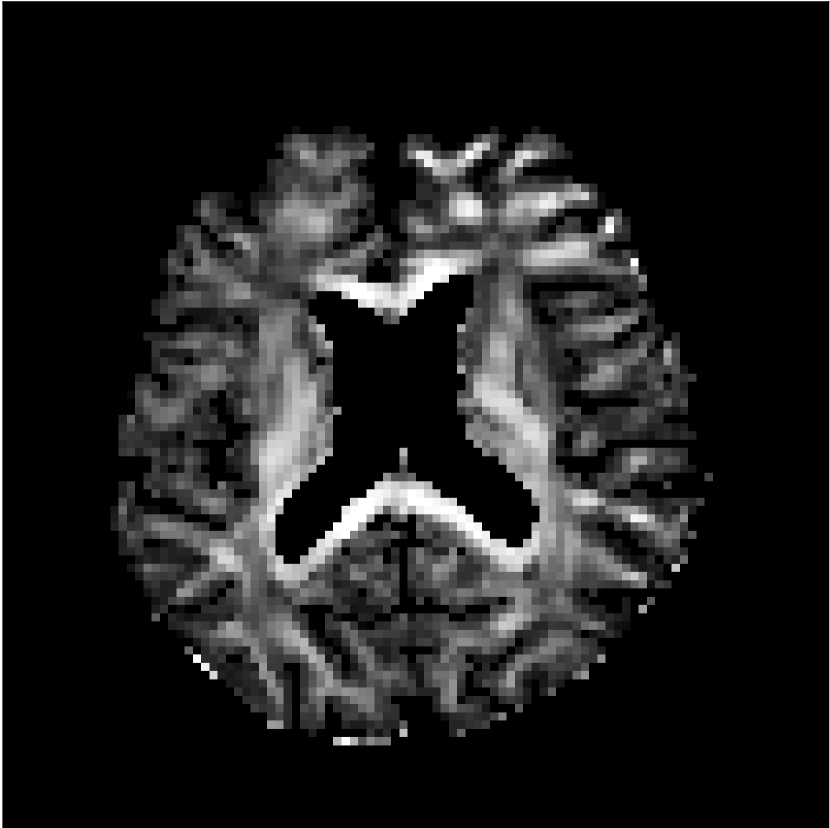

Figure 8 shows examples of non-diffusion-weighted images before and after processing. The raw images (Raw) served as the input for the magnitude deep learning (MCNN) and complex deep learning (CCNN) methods.

Raw 𝐱tsubscript𝐱𝑡\mathbf{x}_{t}

MCNN, fθ^(𝐱t)subscript𝑓^𝜃subscript𝐱𝑡f_{\hat{\theta}}\left(\mathbf{x}_{t}\right)

MCNN Resid., Ric(𝐱t)fθ^(𝐱t)Ricsubscript𝐱𝑡subscript𝑓^𝜃subscript𝐱𝑡\text{Ric}(\mathbf{x}_{t})-f_{\hat{\theta}}\left(\mathbf{x}_{t}\right)

CCNN, fθ^(𝐱t)subscript𝑓^𝜃subscript𝐱𝑡f_{\hat{\theta}}\left(\mathbf{x}_{t}\right)

CCNN Resid., Ric(𝐱t)fθ^(𝐱t)Ricsubscript𝐱𝑡subscript𝑓^𝜃subscript𝐱𝑡\text{Ric}(\mathbf{x}_{t})-f_{\hat{\theta}}\left(\mathbf{x}_{t}\right)

No PF

5/8 PF

Figure 8: Examples of non-diffusion-weighted images from in vivo data at b=0𝑏0b=0 s/mm2. Artifacts in the Raw image, 𝐱tsubscript𝐱𝑡\mathbf{x}_{t}, are corrected by the MCNN and CCNN models, fθ^(𝐱t)subscript𝑓^𝜃subscript𝐱𝑡f_{\hat{\theta}}(\mathbf{x}_{t}). Also shown are the residuals between the CNN corrections and the original Raw image with Rician bias correction Ric(𝐱t)Ricsubscript𝐱𝑡\text{Ric}(\mathbf{x}_{t}) [10]. The Gibbs artifacts removed by the methods are observed in the residuals. The MCNN method introduces some banding artifacts at the PF 5/8ths factor that are not present in the CCNN method.

Both methods remove artifacts, but the MCNN method allows residual rippling artifacts to pass through in the presence of partial Fourier. These rippling artifacts are not present in the CCNN method.